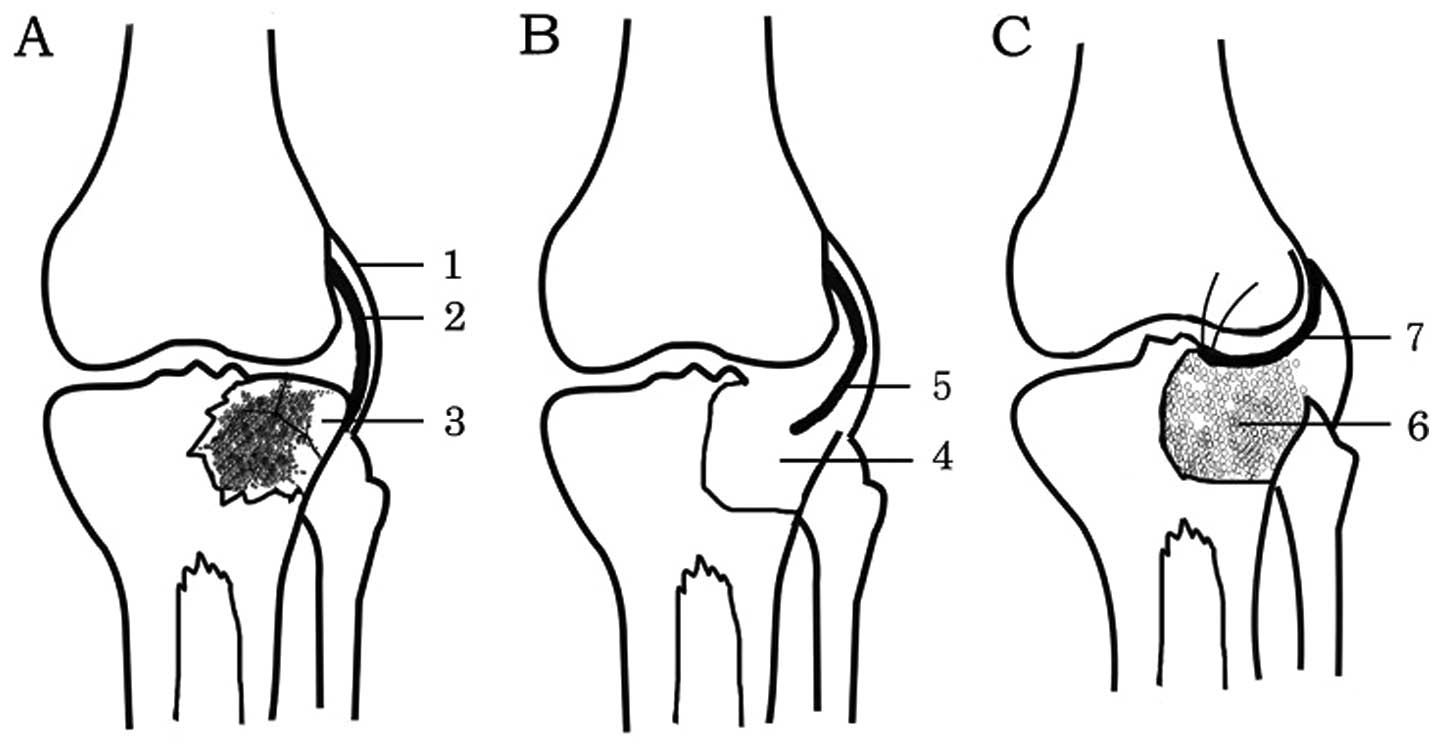

Combined debridement, bone graft and articular cavity sealing using synovium in treating metaphyseal osteomyelitis involving knee joints

The aim of this study was to investigate the efficacy of combined debridement, bone graft and articular cavity sealing using synovium in the treatment of metaphyseal osteomyelitis involving the knee joint. Eleven patients with metaphyseal osteomyelitis, which involved femurs in 4 patients and tibiae in 7, were included. The patients received a novel treatment, which combined debridement, bone graft and articular cavity sealing using the synovium. Of the 11 patients, 4 patients with knee joint instability received a structural allograft and 7 with a stable knee joint underwent a particulate bone graft. The 11 patients underwent regular clinical and radiological evaluation; the average follow-up was 74 months (range, 58-96). Infection recurrence in the joint and bone graft area was not observed in 10 of the 11 cases. In one patient, who underwent a lateral granular cancellous bone allograft in the right tibial plateau, the infection recurred 2 weeks later in the graft area. The infection was arrested 3 months after re-debridement and a bilateral ilium bone graft to eliminate the dead space. Combined debridement, bone graft and articular cavity sealing using the synovium may be a feasible treatment for metaphyseal osteomyelitis involving the knee joint.